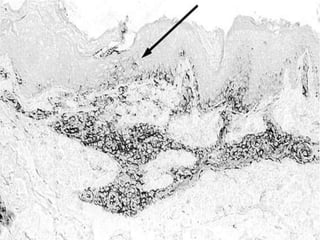

ICAM-1 reactivity in PL skin

• ICAM-1 reactivity in PL skin of vitiligo donor.

Note: the focal epidermal expression (arrow).

ICAM-1 reactivity inPL skin • ICAM-1 reactivity in PL skin of vitiligo donor. Note: the focal epidermal expression (arrow).